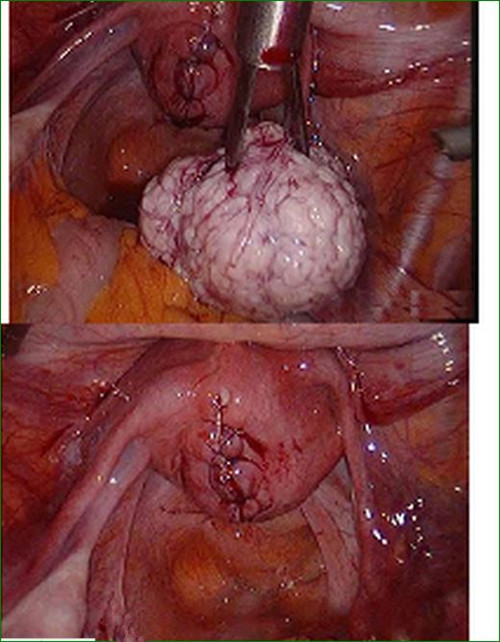

輸卵管囊腫手術

手術後巧克力囊腫

實拍巧克力囊腫

手術後巧克力囊腫的

A:巧克力囊腫如果是直徑>5cm,有手術指徵就需要做手術。一般選擇微創的手術腹腔鏡,把卵巢的巧克力囊腫剝除,術後還要給予長期的規範化管理,否則巧克力囊腫很容易就復發。當巧克力囊腫很小的時候,直徑巧克力囊腫又叫子宮內膜異位囊腫,它的發病原理是由……

A:巧克力囊腫是子宮內膜異位症的一種,會引起進行性加重的痛經,囊腫會隨著時間的推移,逐漸增大,症狀逐漸加重,治療以手術為主,有腹腔鏡和開腹手術方法。具體費用和手術方式、耗材、醫院級別有關係,如果囊腫沒有出現扭轉或者破裂等,手術操作相對簡單,一般……